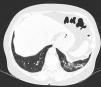

In ILD, there is a decrease in acoustic impedance between the lung air and the soft tissues of the chest wall, because part of the space initially occupied by air volume is replaced by infiltration of inflammatory cells or connective tissue, leading to pleural line disturbances and vertical artefacts called "B-lines". B-lines are indicative of increased subpleural lung density prior to consolidation and may be caused by the presence, not exclusively, of interstitial disease.25 The pleural line becomes irregular and thickened and may appear blurred and fragmented. B-lines are shown as vertical hyperechoic streak-like artefacts arising from the pleural line and extending to the end of the screen without fading, blurring the A-lines, and moving synchronously with the pleural sliding. The presence of multiple B-lines is the defining ultrasound sign of "interstitial syndrome".26Fig. 2 shows a CT scan of a patient with RA and ILD; Fig. 3 shows the ultrasound findings.

Lung ultrasound performed on the same patient as in Fig. 2 with GE Logiq 3 equipment, with 10–14 MHz multifrequency linear transducer, with the patient in a seated position and transducer in longitudinal direction. The arrow points to a B line. The triangle points to the pleural line, which is irregular in appearance. Note the absence of A lines.